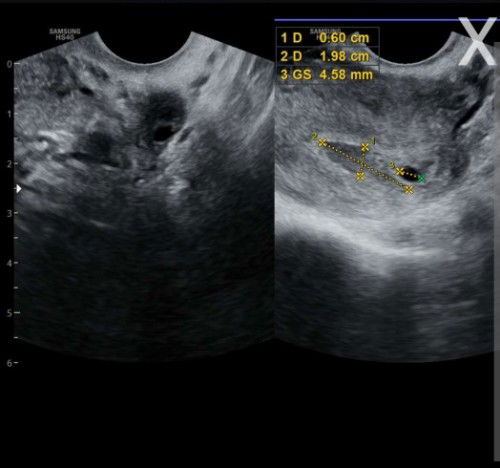

Saya mau tanya apa Ada disini yang pengalaman pendarahan di dekat kantung , disini saya habis USG transvaginal kantung juga ukuran kecil tidak sesuai hitungan HPHT tgl 8agts pada tanggal 19sept ada flek selama 3hari dokter juga bilang ada pendarahan lumayan banyak didekat kantung, jujur agak down, tadi dikasih obat penguat sama vitamin dan hasilnya disuruh balik 2 minggu lagi untuk lihat perkembangan, minta do'anya bunda" 😢😢😢😢#seriusnanya #bantusharing